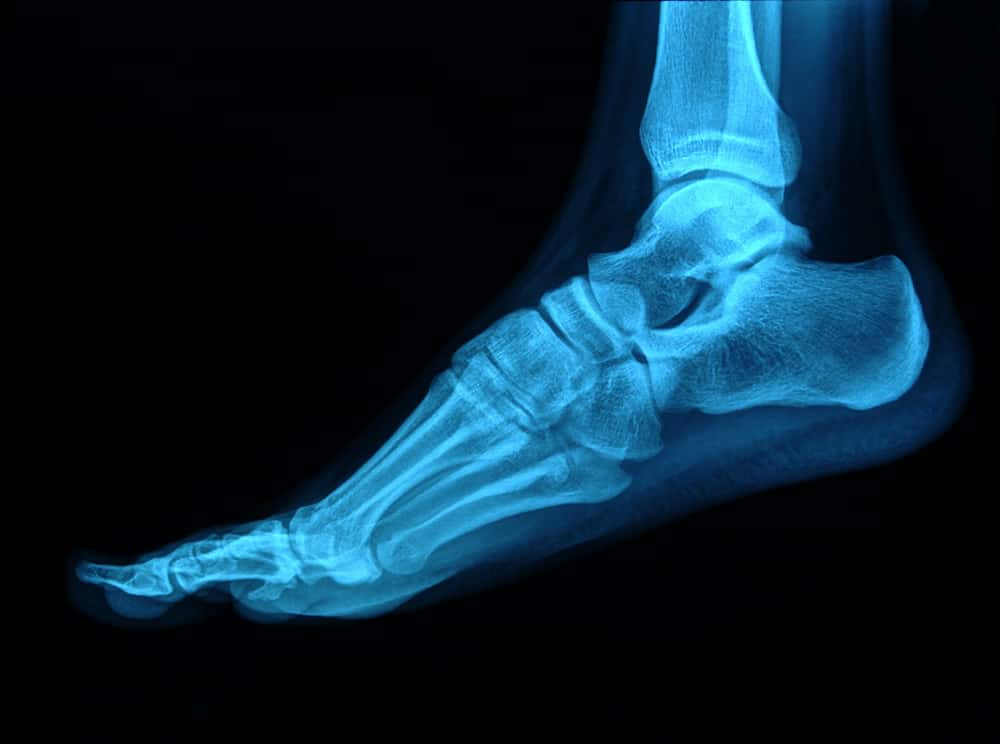

Often, a diagnosis can be made by asking some specific questions and through a physical examination (if available). However, if the hospital suspects you may have fractured your ankle, they will arrange an X-ray to check your bones.

If you have been to the hospital and an X-ray has revealed that you have fractured your ankle, you will usually be asked to see a specialist orthopaedic (bone and joint specialist) doctor do discuss your options.

You will normally be seen or spoken to by the hospital before removing the cast. Sometimes, you will have another X-ray to check the progress of your ankle, but this is not always the case.